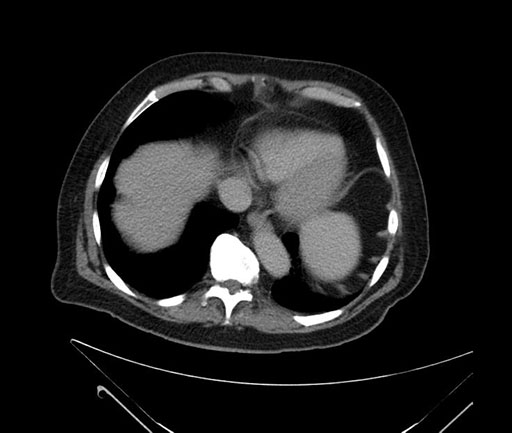

Whipple (pancreaticoduodenectomy) [case 7]

Imaging Analysis

Look through the patient's CT scan to identify any areas of concern for the necessary procedure.

Based on your CT findings, which issue(s) would give reason for "planned slowing down moment(s)" in this case?

Considering a standard Whipple procedure, what step(s) of the operation would you do differently in this case?